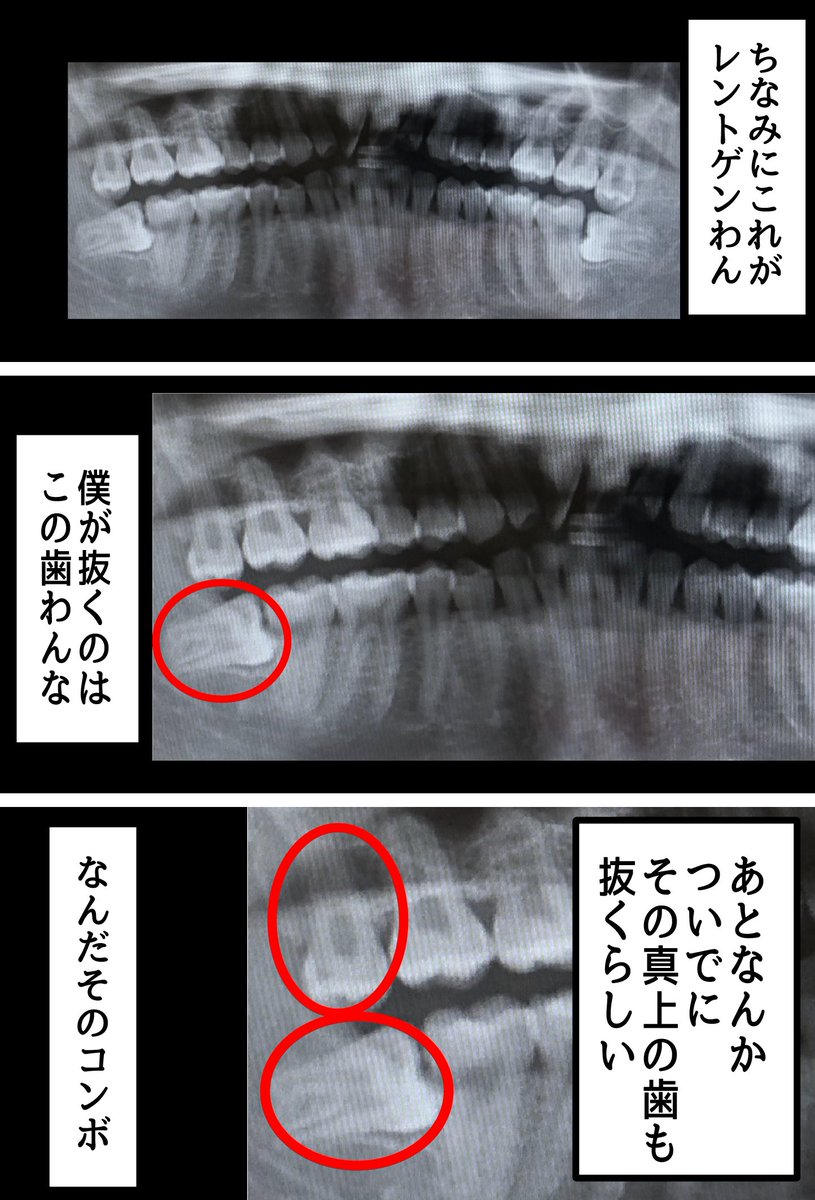

近況報告